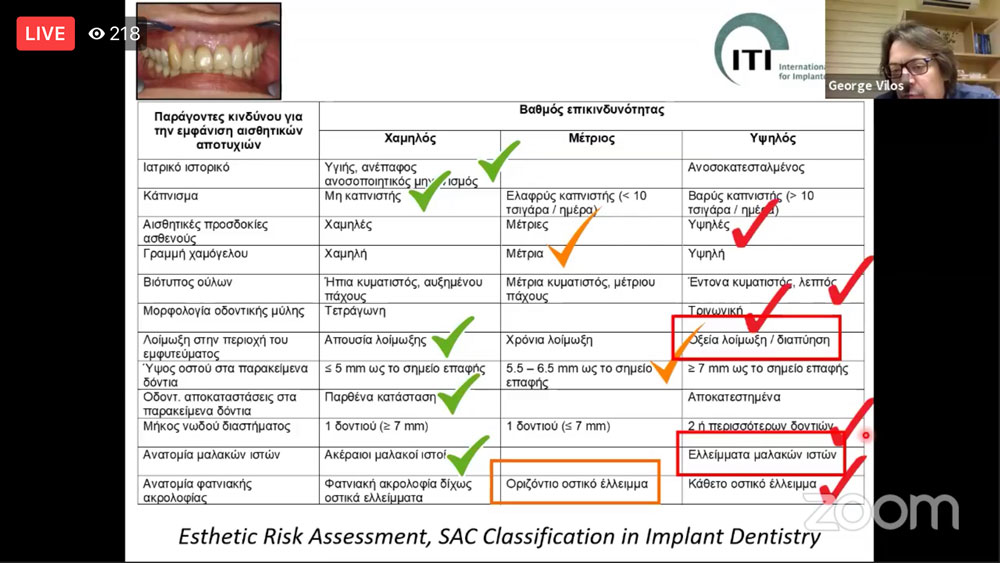

Ενώ το τρίτο και τελευταίο κατά σειρά κλινικό περιστατικό ανήκε στον γναθοχειρουργό Γιώργο Βήλο και αφορούσε γυναίκα 42 ετών, την οποία παρέπεμψε σε αυτόν η προσθετολόγος προκειμένου να αξιολογήσει τον κεντρικό και τον πλάγιο της δεξιάς πλευράς, τον #11 και τον #12. Η ασθενής είχε ελεύθερο ιστορικό ήταν μη καπνίστρια. Ιστορικό Ε.Θ. (#12,11,21) και ακρορριζεκτομών (#12,11) ενώ η ασθενής όταν προσήλθε στην προσθετολόγο είχε φλεγμονώδη διόγκωση στην περιοχή που υποχώρησε όμως με την λήψη αντιβιοτικών. Στην κλινική εξέταση παρουσίασε εκροή πυώδους εξιδρώματος από συριγγώδη πόρο στη φατνιακή ακρολοφία.

Όλα τα στάδια που ακολουθήθηκαν στα περιστατικά παρουσιάστηκαν βήμα-βήμα μέσα από φωτογραφίες. Η διάδραση μεταξύ των ομιλητών και του κοινού